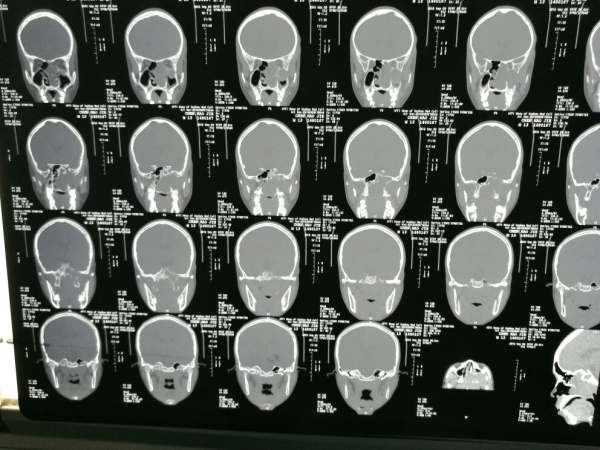

CT显示:左侧前中颅底部示不规则团块影,边界不清,密度欠均匀,临近骨质压迫、吸收,局部骨质欠连续,病变向筛窦、蝶窦、左侧鼻道、鼻咽腔、左侧眼眶及左侧颅内突出,与左侧海绵窦分界不清,左侧蝶窦、上颌窦及筛窦、左侧鼻甲形态不整,鼻咽腔变窄。

MR显示:左侧鼻咽腔、翼腭窝及筛窦富血供伴颅底骨破坏

初步诊断:鼻咽纤维血管瘤(Ⅳa期)。